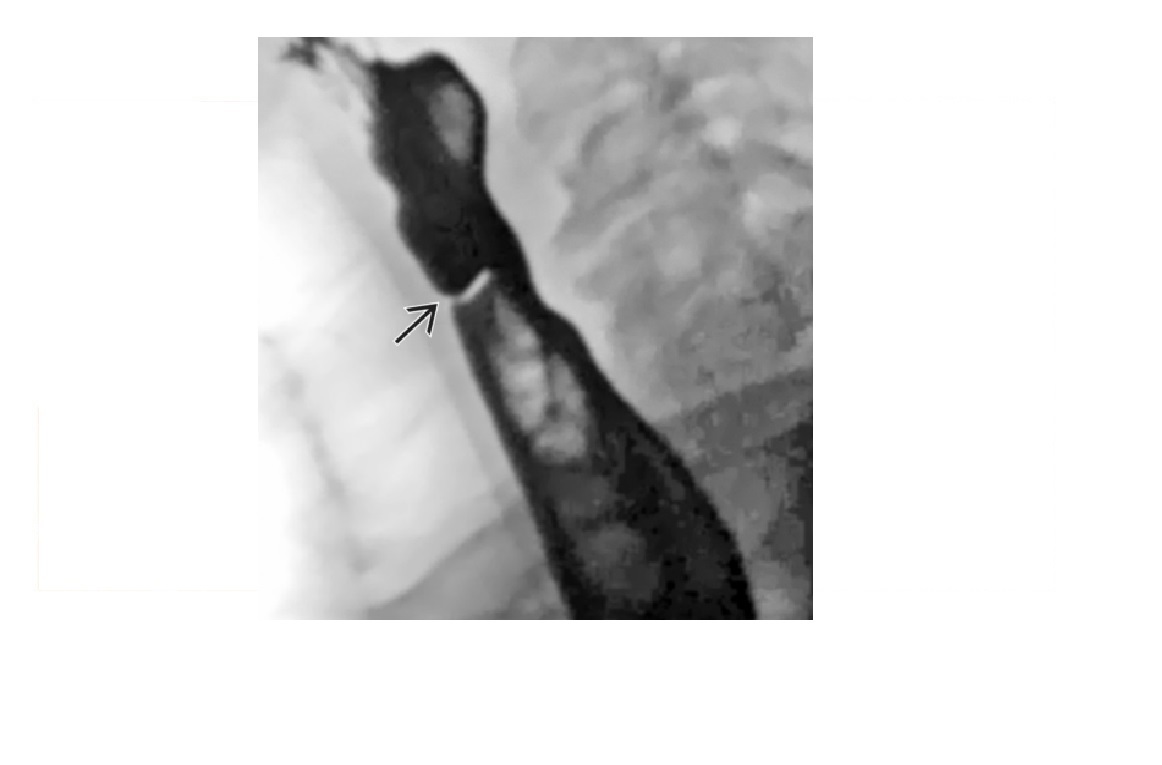

Zenker Diverticulum

Outpouching with rounded contour posteriorly in the neck is above the cricopharyngeus muscle

In hypopharynx!!!

Site of weakness is the Killian dehiscence - between the inferior pharyngeal constrictor muscle and cricopharyngeal muscle